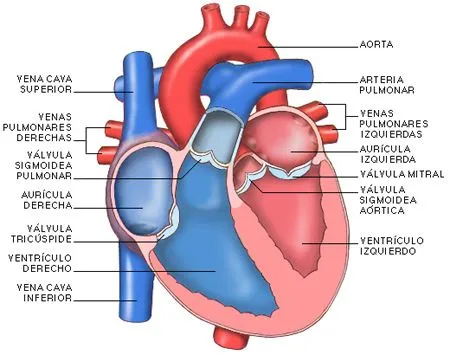

Fotos - El Corazón y sus Partes | Fotos e Imágenes en FOTOBLOG X